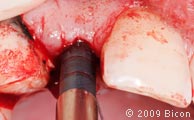

18. Введение имплантата 4.5х8.0мм в лунку с помощью специального инструмента.

19. Введение имплантата 4.5х8.0мм в лунку с помощью специального инструмента.

20. С помощью посадочного адаптера и прямого держателя имплантат досаживают до конца методом постукивания.